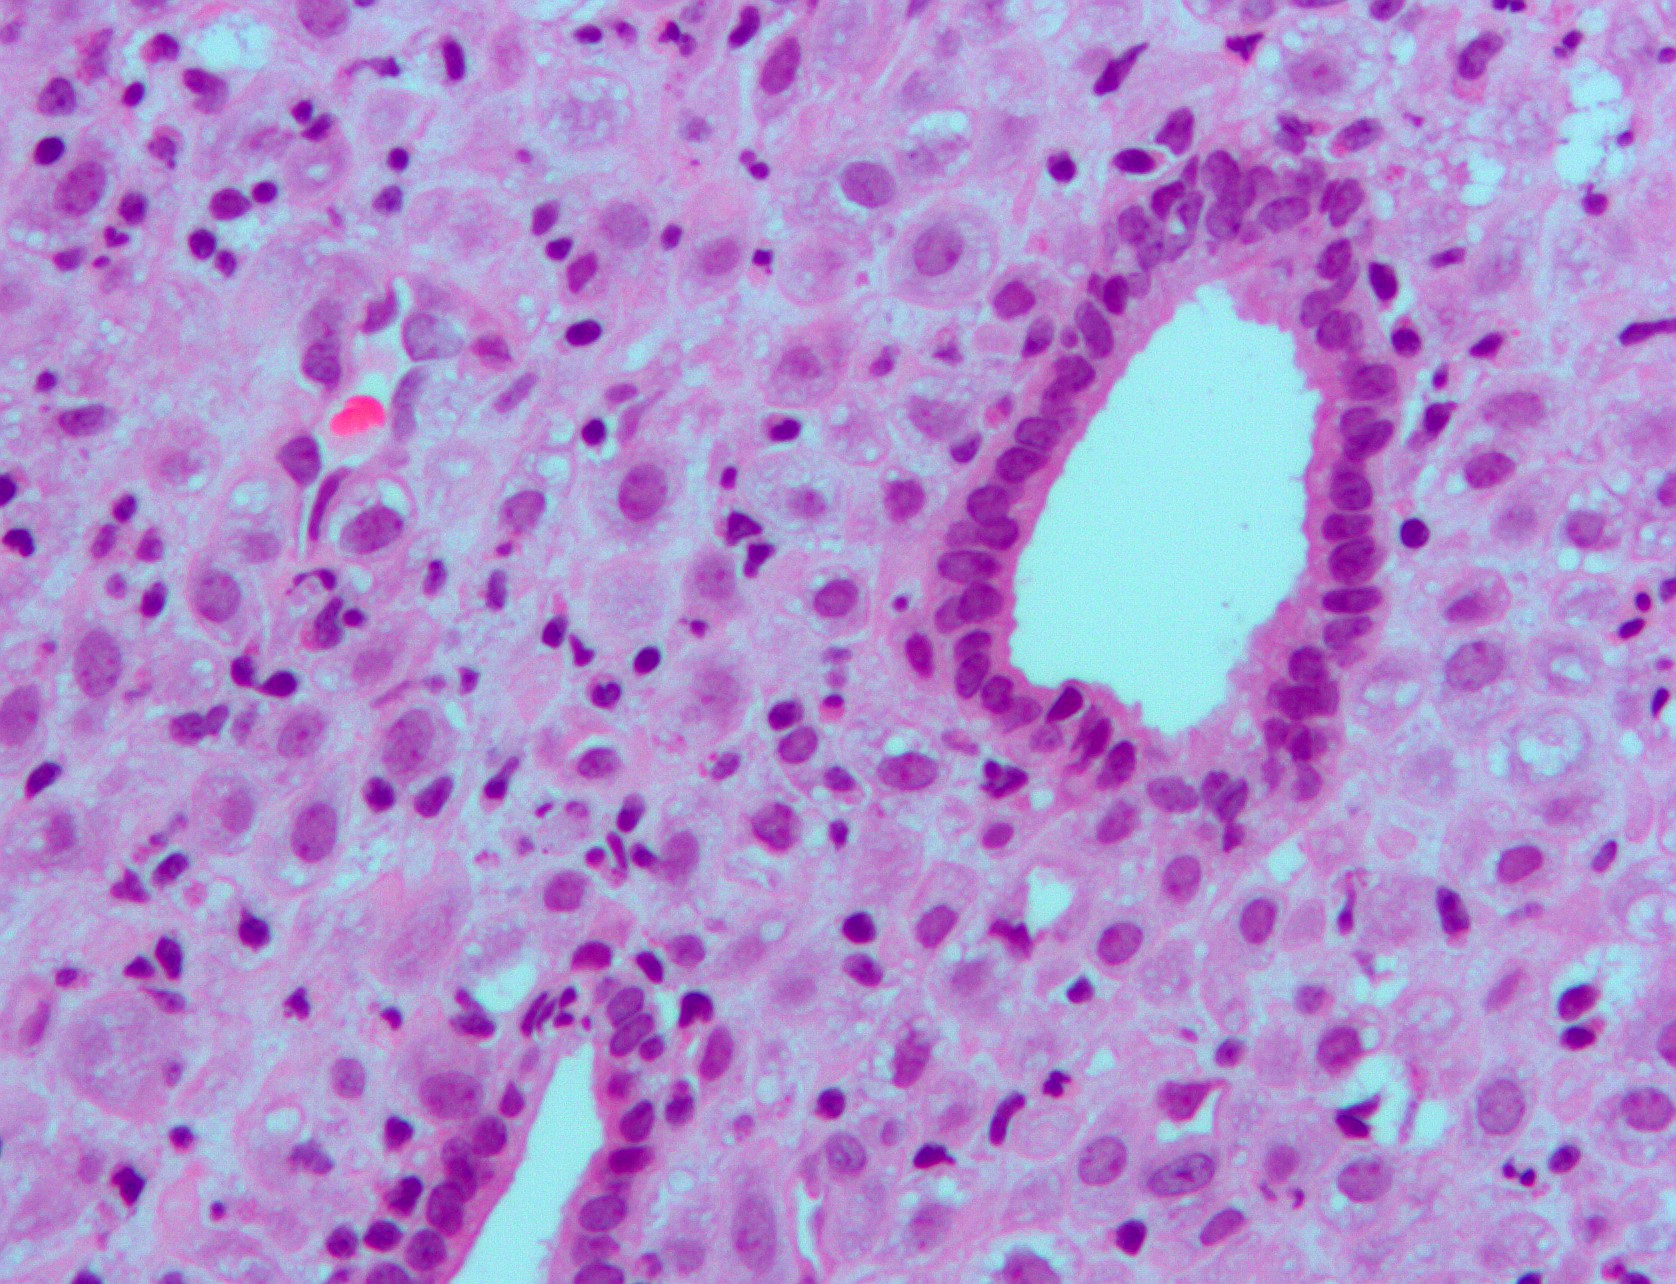

Le patologie riproduttive femminili - ad esempio alterazioni del ciclo mestruale, endometriosi e aborti, nati pretermine e sottopeso - possono essere correlate all'azione delle sostanze perfluoroalchiliche (PFAS) sulla funzione ormonale del progesterone, ormone femminile che agisce a livello dell'utero.

L'analisi sulle cellule endometriali in vitro ha dimostrato che i PFAS interferiscono vistosamente sulla regolazione dei geni espressi a livello dell'endometrio; su più di 20.000 geni analizzati, il progesterone normalmente ne attiva quasi 300, ma la ricerca ha riscontrato che in presenza di PFAS ne vengono alterati 127, tra cui quelli che preparano l'utero all'attecchimento dell'embrione e quindi alla fertilità.

Immagine di copertina: endometrio (Autore: Nephron - Fonte: Wikipedia)